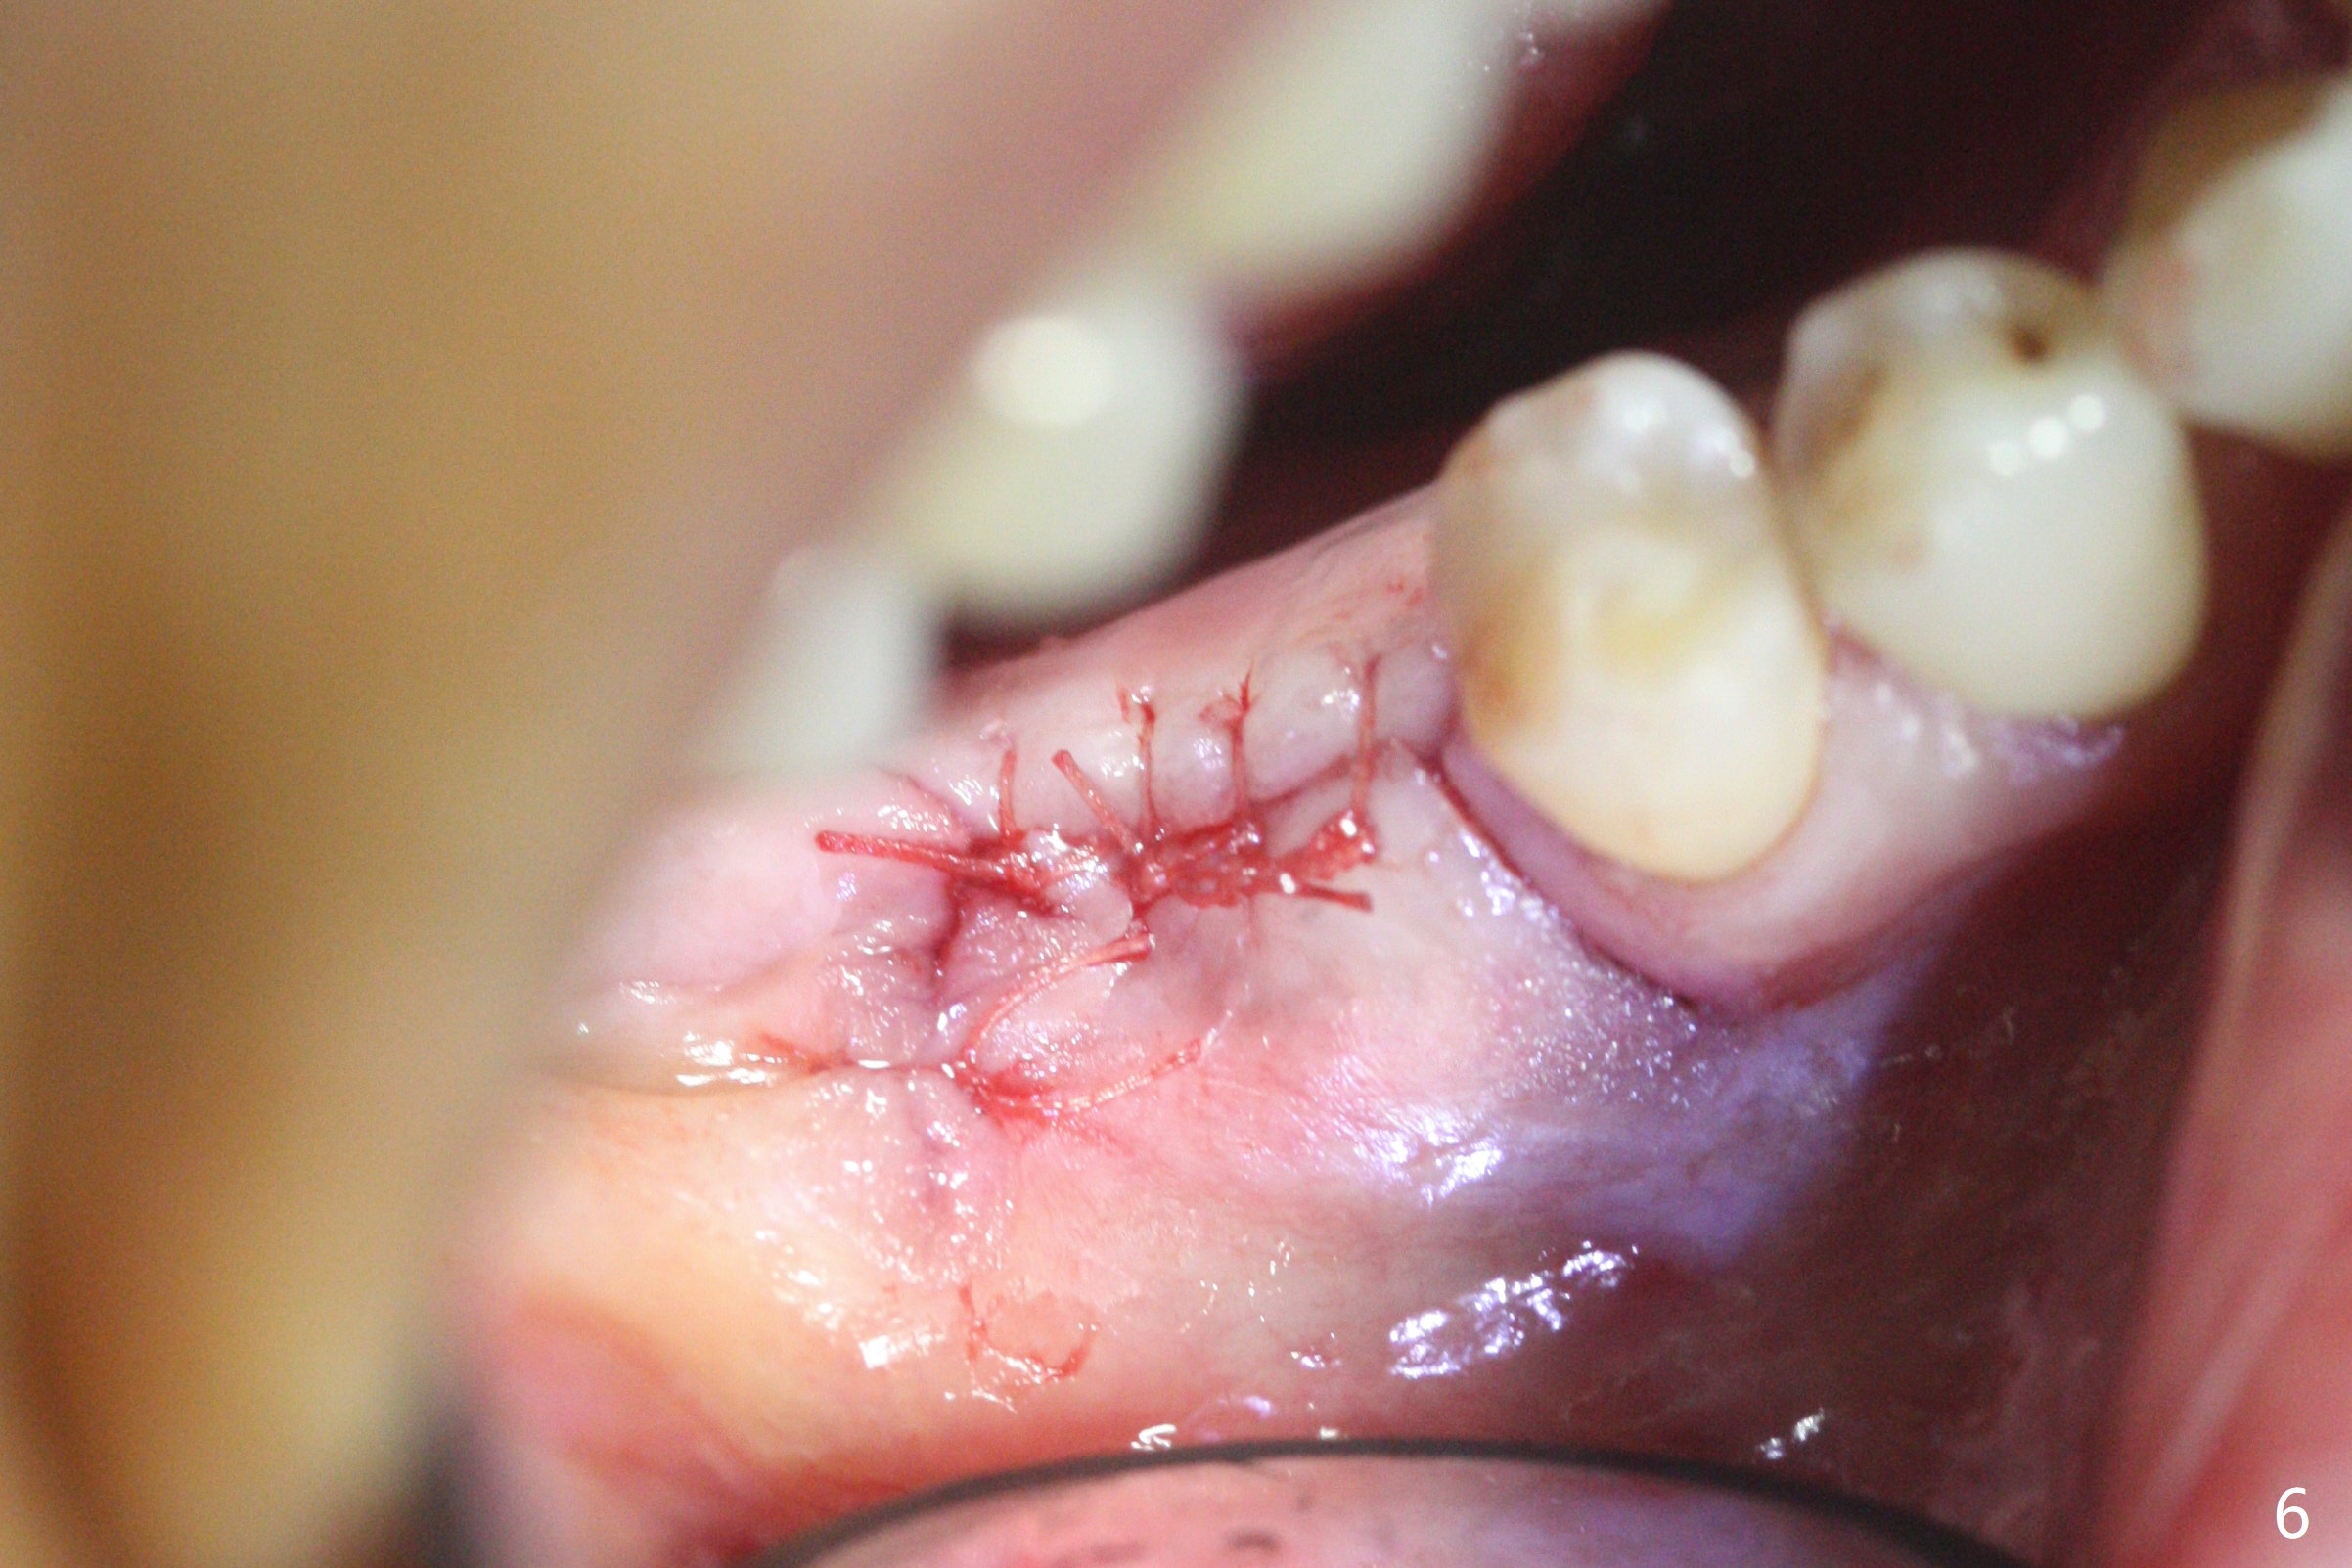

74岁女,右下6因植牙周围炎,植体取出,植骨,术后14个月回来做导板植牙术,局部infiltration时,发现位点中央有些分泌物,刮匙证实有一个瘘道(图一),翻瓣似乎不可避免,骨质缺损没有完全愈合(图二),其实仔细温习术前CT也能发现缺损(图三),导板钻洞位于缺损近中(图四:白圆圈),随着钻头直径增大,钻洞会偏移远中(图四:箭头)和颊侧(由于舌侧骨板厚,颊侧骨板低)。因此用过4毫米钻头后,植入4毫米报废IS植体,接近颊侧。同时为了防止植体断裂,选择五级钛植体(图五)。由于扭力低(手植入,有间隙:图五:<),包埋,使用自体骨和异体骨(皮质,*)。覆盖Osteogen tape后,PGA缝合,牙周胶水(图六)。如果植入4.5毫米植体,后者会更偏移远中。